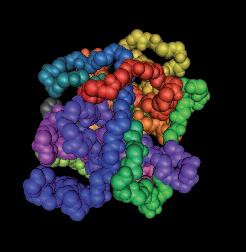

La pagina a fianco mostra l'immagine di una cellula tumorale reale, visualizzata al microscopio elettronico, che ingrandisce questa cellula 6500 volte rispetto alle sue normali dimensioni. Questo tipo di cellula prende il nome di carcinoma, cioè derivante da cellule epiteliali, il tipo di cellule che rivestono sia le superfici interne (polmoni, intestini) che esterne (pelle) del corpo.

Grazie a questo ingrandimento si possono identificare chiaramente alcune delle caratteristiche di tutte le cellule tumorali: a) l'enorme nucleo cellulare dalla forma insolita che spiega la loro grande capacità di riprodursi e b) la struttura non uniforme, complessa della superficie cellulare, che riflette una forte attività di secrezione di sostanze prodotte dalle cellule tumorali.

Una delle più importanti molecole secrete dalle cellule tumorali in grandi quantità sono gli enzimi a ‘forbice’ che digeriscono il collagene. Sono aggiunti graficamente a questa immagine, sotto forma di strutture simili ad un ‘pacman’ rosso.

Naturalmente questi sfere, nella vita reale, sono molecole biologiche, proteine, che hanno la capacità di tagliare le fibre di collagene e di altre molecole del tessuto connettivo. L‘immagine sopra mostra che non c’è un solo tipo di 'pacman' ovvero di queste molecole, ma

Digestione del tessut o connet tivo del tessuto connetti vo diversi tipi, quali il plasminogeno/plasmina e le metalloproteasi (strutture colorate tridimensionali). Queste molecole migliorano il loro effetto distruttivo attivandosi reciprocamente in forma di reazione a catena in cascata.